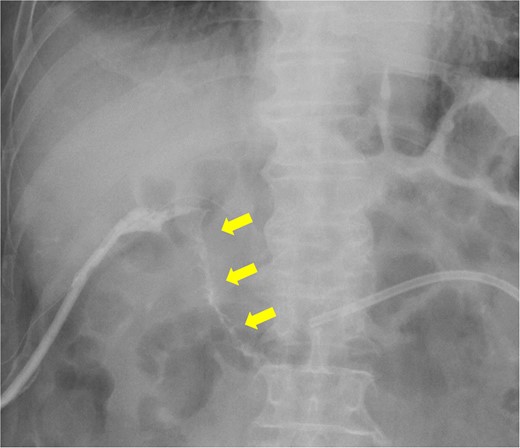

The amylase levels of drainage fluid and blood at postoperative day (POD) 1 (Ascites 6980 IU/dl, Serum 1123 IU/dl) and POD 3 (Ascites 673 IU/dl, Serum 487 IU/dl) revealed pancreatic fistula based on the criteria of International Study Group of Pancreatic Fistula [2]. After that, their results improved, and fluoroscopy showed no stenosis and leakage. Therefore, we removed all drains at POD 8, however the following day, the patient developed high fever. Plain CT revealed intraperitoneal fluid around subdiaphragmatic and duodenal stump (Fig. 3). We inserted a pig-tail drainage tube to the subdiaphragmatic space (Fig. 4). Since biliary fluid was discharged through the tube, we suspected duodenal leakage and started infusion of somatostatin analogs and antibiotics. At POD 13, the patient complained of whole abdominal pain with peritoneal signs. As the patient became hemodynamically unstable, we performed emergent laparotomy to lavage and insert multiple drainage tubes. Two perforation pinholes were identified in the anterior wall of the duodenum, near the stump. We resected the vulnerable duodenal stump including the perforation site and closed by Gambee’s method with unabsorbable 4–0 proline (Fig. 5). We inserted multiple drainage tubes (Fig. 6a): a C-tube from the cystic duct into the common bile duct to separate biliary juice and pancreatic juice, a dual drainage tube around the duodenal stump with continuous suction (Fig. 6b), a simple intraluminal drainage tube via the duodenum near the stump through a new skin incision on the left side of the abdomen for duodenal decompression, and a drainage tube into the rectovesical pouch. After the reoperation, we irrigated the cavity around the duodenal stump through each drain with saline. Since the contrast agent did not flow into the duodenum and the cavity around the duodenal stump gradually got smaller (Fig. 7), oral intake of fluid diet was initiated at POD 37. However, fistulography at POD 44 showed that the fistula of duodenal stump had relapsed (Fig. 8). Although we considered performing second reoperation for duodenal stump closure, due to the cavity around the duodenal stump was located, we continued conservative management and irrigation via drainage tubes. Fistulography demonstrated no leakage from the duodenal stump at POD 56, and the patient discharged at POD 59.

Fistulography reveals recurrence of the duodenal fistula. Fistulography at POD 44 showed recurrence of the duodenal fistula (arrows).